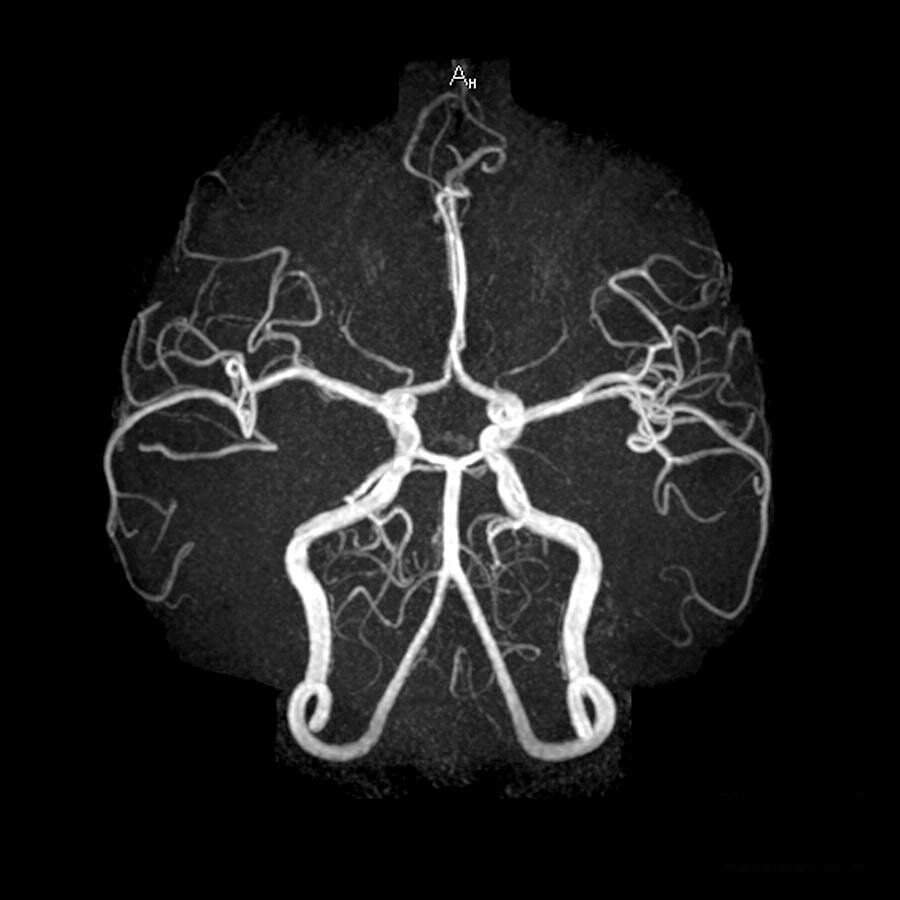

Ангиография виллизиевого круга

МРА (магнитно-резонансная ангиография)